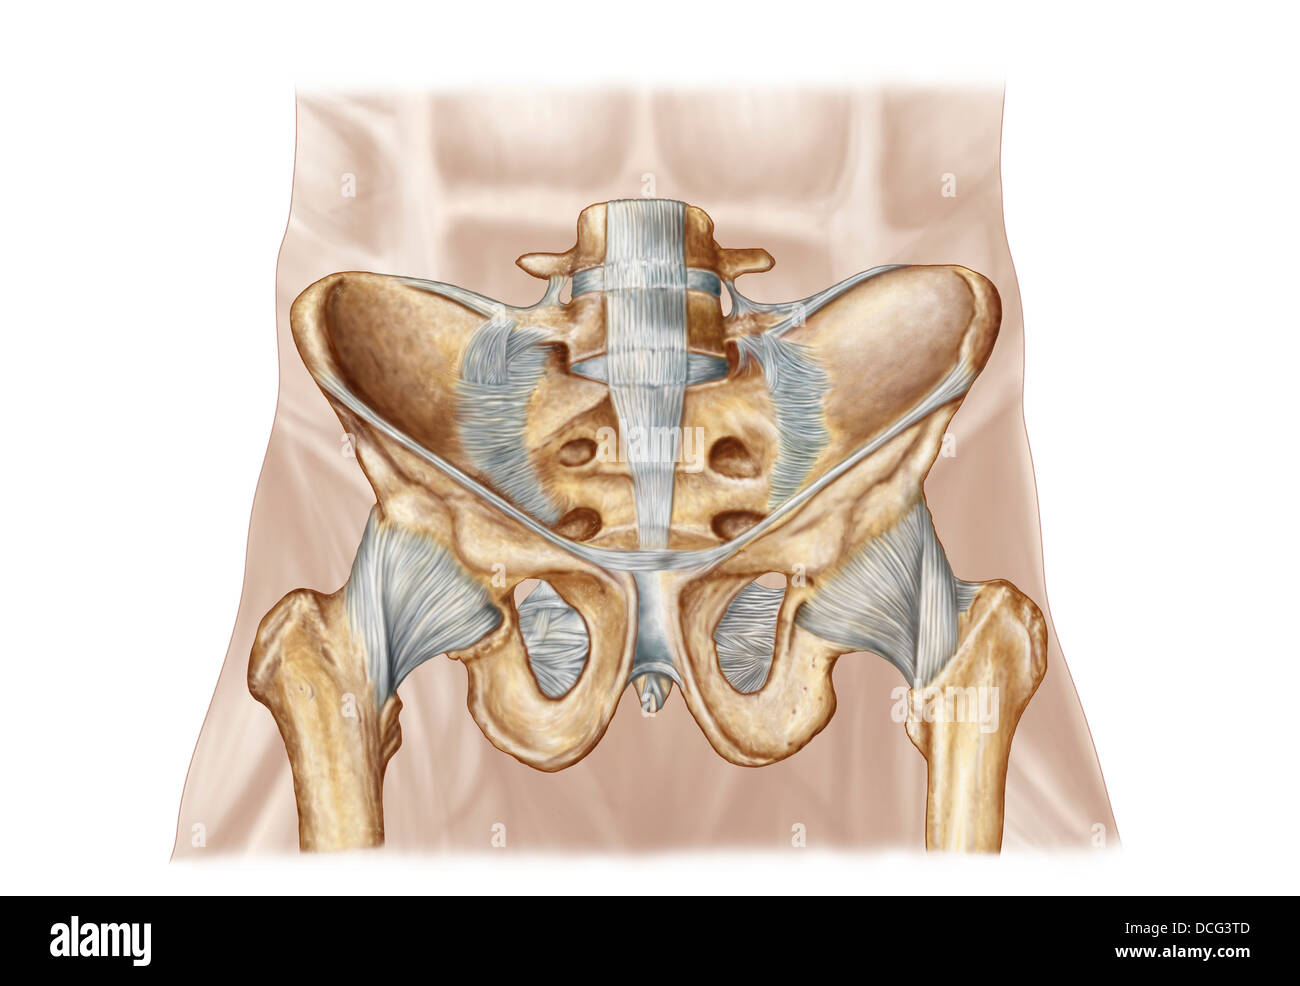

Anatomy of human pelvic bone and ligaments. Stock Photohttps://www.alamy.com/image-license-details/?v=1https://www.alamy.com/stock-photo-anatomy-of-human-pelvic-bone-and-ligaments-59361245.html

Anatomy of human pelvic bone and ligaments. Stock Photohttps://www.alamy.com/image-license-details/?v=1https://www.alamy.com/stock-photo-anatomy-of-human-pelvic-bone-and-ligaments-59361245.htmlRFDCG3TD–Anatomy of human pelvic bone and ligaments.